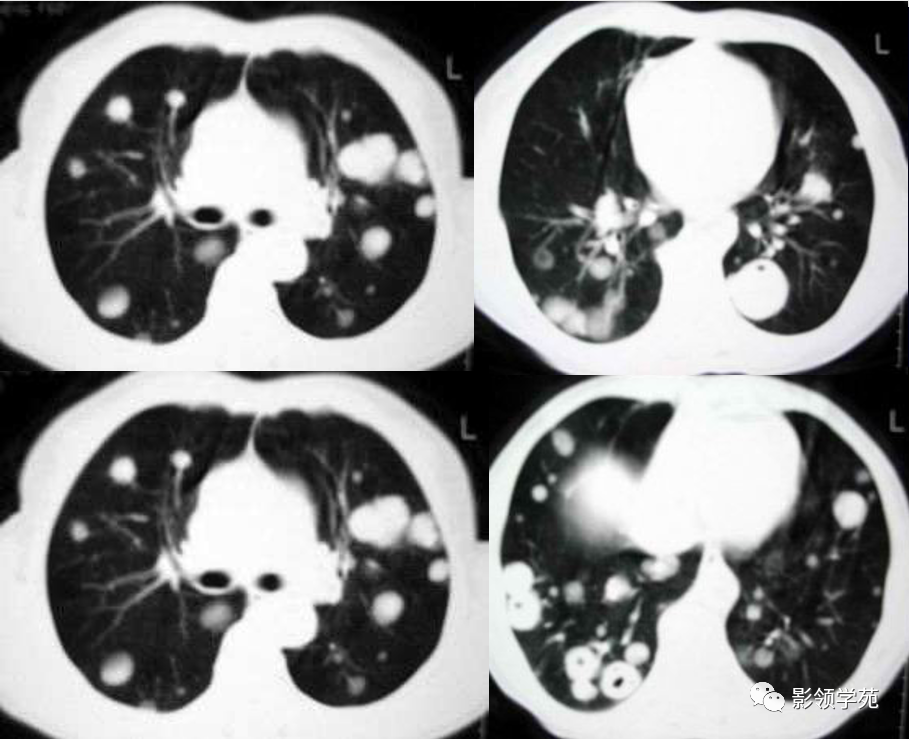

血行转移:双肺多发密度一致、大小形态不一结节状影(下图)

1. 血行性转移 :多发或单发结节,大小不一,边缘较清楚。少数结节伴出血时出现晕轮征,即有略高密度影像环绕结节,使病变边缘模糊。病变有钙化常见于骨肉瘤或软骨肉瘤转移。转移瘤亦可表现为空洞。两肺多发的小结节影具有随机分布的特点,HRCT显示结节位于小叶中心、小叶间隔、支气管血管束及胸膜,结节大小不均匀。

肺转移瘤。

肺窗像(A)示双肺野可见大小不等的圆形高密度结节影,纵隔增宽;纵隔窗像(B)示肺内肿块呈实性,纵隔满布大小不等的肿大淋巴结